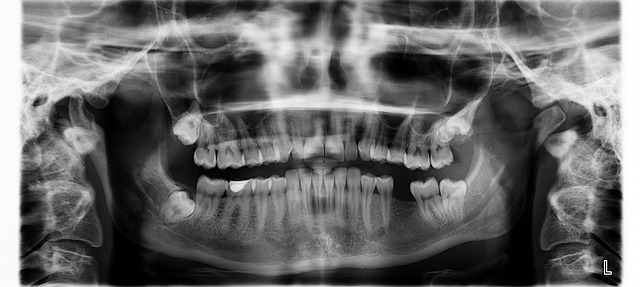

Planlama Aşaması

Detaylı ağız içi muayene ve radyolojik görüntüleme yapılır. Üç boyutlu tomografi ile kemik yapısı, sinir ve damar konumları incelenir. Hastanın genel sağlık durumu değerlendirilir ve kullandığı ilaçlar gözden geçirilir.